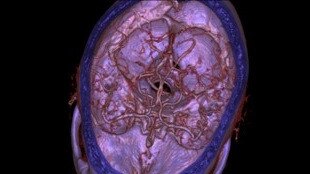

Vasküler Görüntü Galerisi